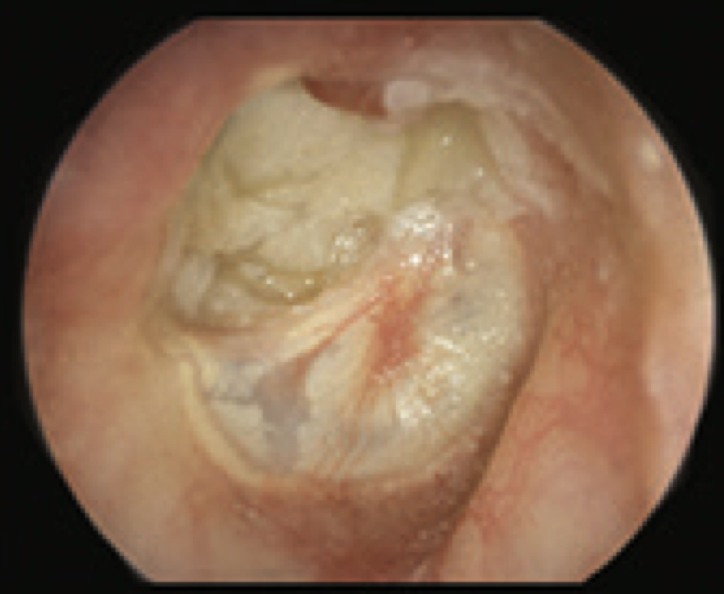

10

Q

What is this?

A

Tympanosclerosis

- intact TM

- deposition of calcium